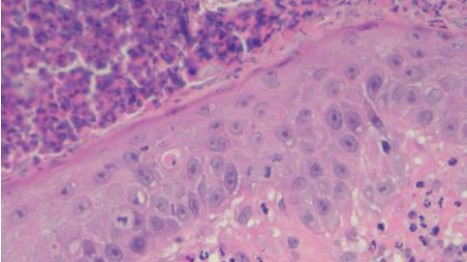

組織病理結果為化膿性嗜酸球性真皮炎,如圖四所示。排除感染的問題,提高prednisolone劑量到3mg/kg sid,兩週後硬皮病灶消失、搔癢症狀緩解,開始逐漸減量類固醇,目前1mg/kg qod狀況良好如圖五所示,持續治療。

A B

C D

圖四:A, 檢體為表皮層到真皮層組織,少部分表層皮下脂肪有涵蓋在檢體內。B, 表皮結構完整,表面有大量的壞死細胞碎片、片狀角質、脫落的角化細胞覆蓋或是形成沒有破裂的膿皰結構,皮膚糜爛但局限於表皮,基底膜完整。C, 真皮層輕微水腫,有少量到中等量、零散分布的發炎細胞浸潤,細胞有略微分布表層真皮或是毛囊腺體周圍的傾向,但不明顯。D, 浸潤的細胞以嗜中性球、嗜酸性球以及肥大細胞為主,血管內也可見到數量明顯增加的嗜中性球及嗜酸性球,皆為分化成熟沒有惡性特徵。D, 表皮層中有見到一顆凋亡細胞 (apoptotic cell),但周邊沒有淋巴細胞包圍。E, 此外毛囊腺體的結構完整,沒有破裂,毛囊內也沒有見到細菌、黴菌或是寄生蟲。以特殊染色B&B檢查檢體,沒有見到細菌病原。